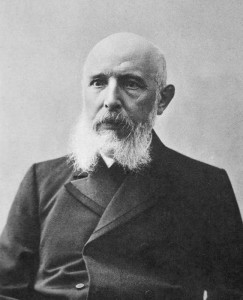

When Gerhard Henrik Armauer Hansen described leprosy In Leprosy: in its Clinical and Pathological Aspects, he examined a section of fresh nodules under the microscope and observed small straight rods in the fluid of the preparation. These were the lepra bacilli that he first discovered in 1871 (Hansen et al., 1895, p. 31). In a fresh preparation, they could be observed to be moving actively. He described them in larger or smaller clumps of a brownish colour that were very granular. They were in the cells and in all the other organs affected with leprosy. He suggested that they may very well serve as a diagnostic indication for leprous affections because, in his experience, they were always present, except in very young nodules.